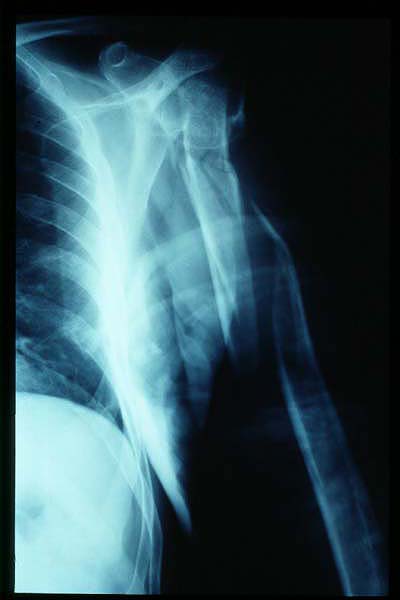

Fractura de húmero, intensa desviación de fragmentos

Fractura de húmero.

Fractura compleja de húmero.